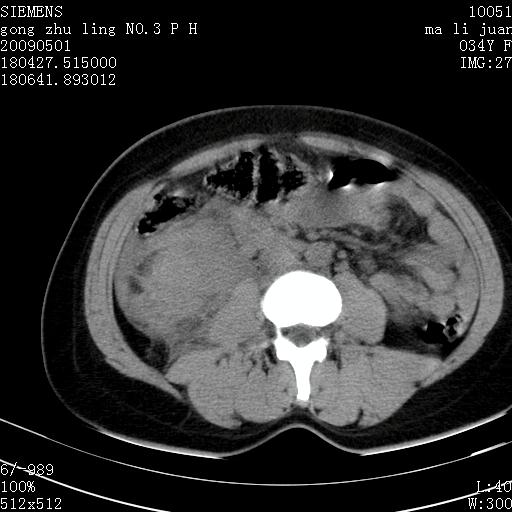

标题: CT19733:右肾碎裂

青年女性,骑摩托车摔伤。

右肾碎裂伤,包膜下血肿。

术中仅见右肾碎裂,肾蒂血管未见断裂。